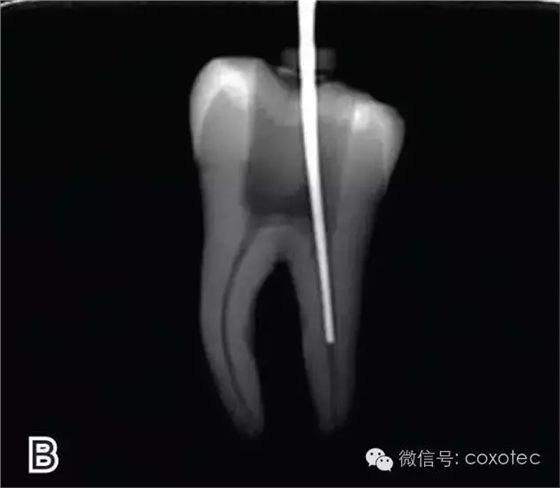

選擇的小號垂直加壓器應能自由到達距根尖4~5 mm(有學者提出3~4 Mm)的位置并能輕微接觸根管壁;中號垂直加壓器應能自由到達距根尖7~8 mm的位置并能輕微接觸根管壁;大號垂直加壓器應能自由到達距根尖10~11 mm的位置并能輕微接觸根管壁。用橡皮片做好標記(圖2)。

圖2 選擇垂直加壓器,A.試垂直加壓器 B.垂直加壓器在根內的位置 選擇非標準牙膠尖(如0.04、0.06 錐度牙膠尖)作為主尖,型號一般與根管預備最大號的器械型號一致,能到達距根尖0.5~1 mm 處,主尖尖段與根管壁緊密接觸。拍試尖X 線片進行確認(圖3)。